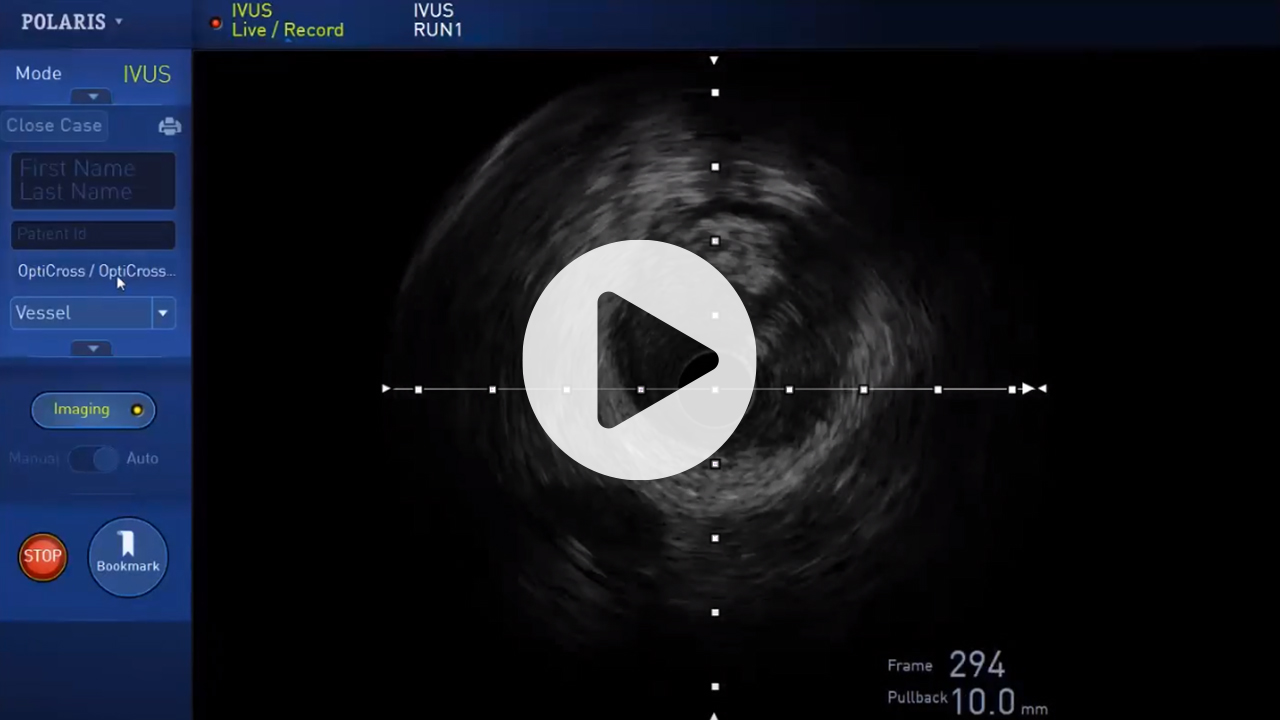

IVUS technology enhancements, including AI-enabled lesion assessment, make PCI optimization achievable, efficient, and, increasingly, a standard of care for Modern PCI. See why current IVUS users choose IVUS to improve their effectiveness and deliver exceptional results for PCI patients.